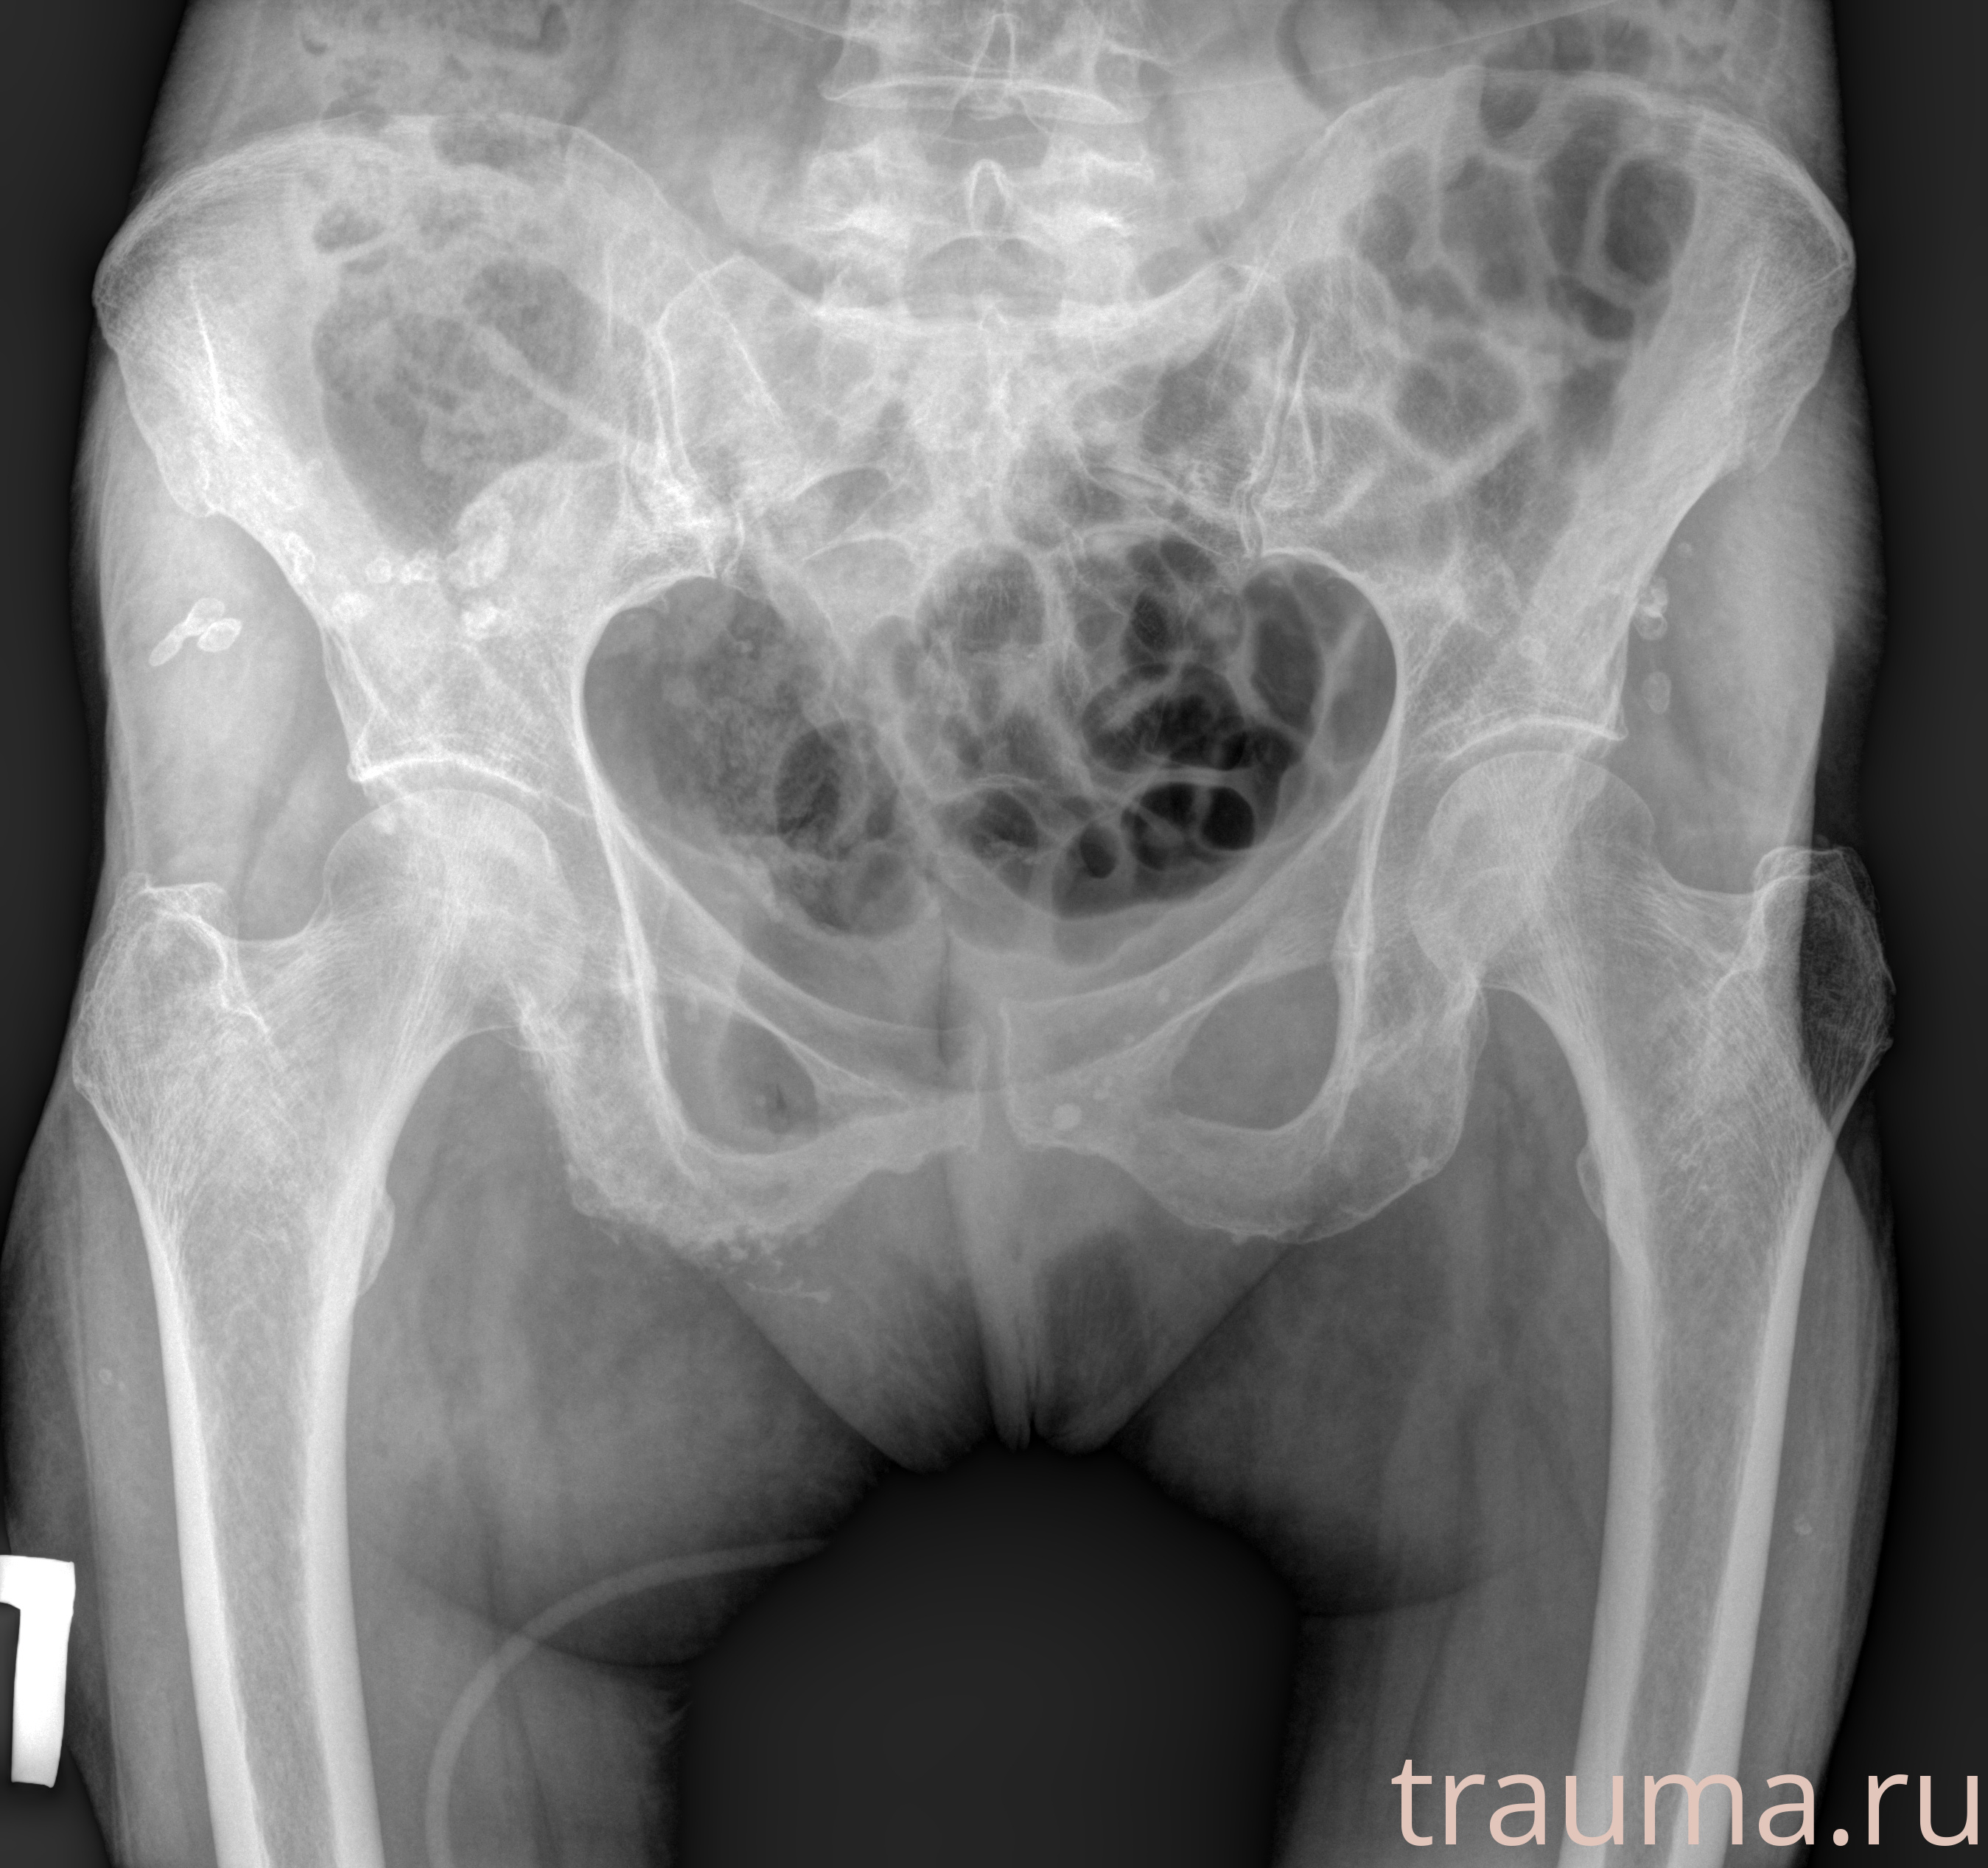

Рентгенограммы

Рентген на дому: по вашему адресу приезжает врач-рентгенолог, травматолог-ортопед с мобильным рентгеновским аппаратом, проводит диагностику травмы или заболевания, делает необходимые рентгенограммы, дает рекомендации по дальнейшему лечению. Получить качественные снимки в домашних условиях возможно благодаря уникальной методике, разработанной МосРентген Центром для института  Склифосовского